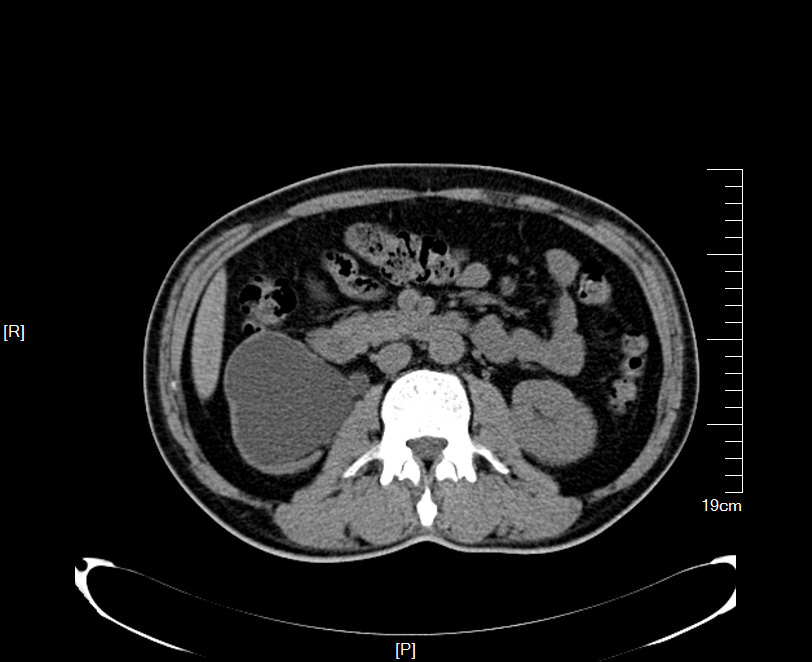

2016年02月手术患者,男性,47岁,河北人,农民,主诉双侧腰部酸胀一年余,伴尿少三天;五年前曾因输尿管结石在当地予以震波碎石3次,后疼痛缓解后未重视,五年来未予以复查,三天前出现尿少,腰部酸胀加重与当地医院就诊后发现病情危重遂来我院求诊,CT:双侧肾脏重度积水,皮质菲薄,双侧输尿管上段扩张明显,双侧输尿管中段结石,左侧结石约1.7cm,右侧约2.8cm左右,GFR:左侧11.7ml/min,右侧16.1ml/min。肾功能:Cr 516umol/L;术前诊断:双侧输尿管结石 双肾重度积水 肾功能失代偿;行双侧经皮肾穿刺造瘘术,保护肾功能,十天后Cr下降至236umol/L,方行双侧输尿管镜检,但由于输尿管梗阻时间太长,输尿管迂曲扩张明显,中段输尿管与周围脏器严重黏连,输尿管镜无法顺利上行,遂行双侧输尿管切开取石术+双侧输尿管裁剪成型术。

CT检查提示:双侧肾脏重度积水双侧输尿管中段结石 双侧输尿管上段积水扩张